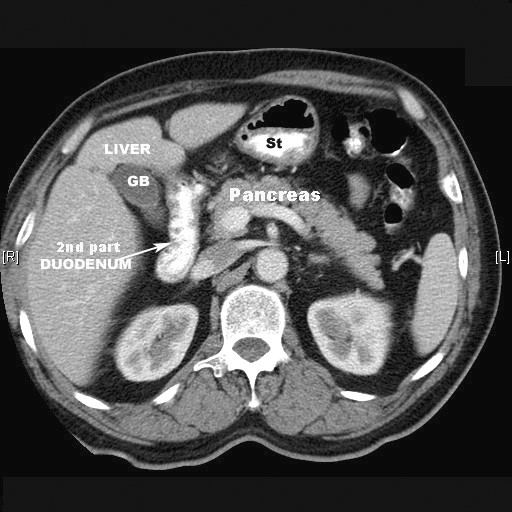

- The second part

- From neck of Gall bladder to L3

- Descending part

- 8-10 cm long

- It is a retroperitoneal structure.

- Contains the ampulla, into which the pancreatic duct and common bile

duct drain.

2nd part duodenum

- Anterior

- Liver

- Transverse colon

- Jejunum

- Posterior

- Right kidney

- Right renal vein

- IVC

- Psoas

- Mediallly

- Head of pancreas

- Bile duct

- pancreatic duct